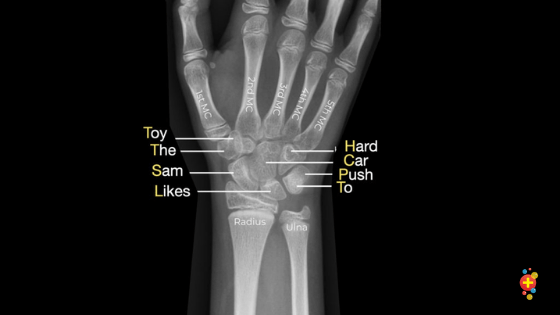

The hand has eight carpals. Presentation2 Pptx Wrist Joint

The lunate is one of these eight carpal bones. He is a clinical professor at the university of washi. Located within the foot, the calcaneus is also known as the heel bone. Mark gurarie is a freelance writer, editor, and adjunct lecturer of writing composition at g. Rachael is a freelance healthcare writer and critical care nurse based near cleveland, ohio. It is a small, freestanding, bone that rests between the femur (thighbone) and tibia (shinbone). Trauma to this area can result in brain injury. It sits on the radial or lateral side of the wrist near the thumb. It is the largest bone in the wrist's proximal row. The malleus is the outermost and largest of the three small bones in the mid. Bones make up the skeletal system, helping to connect, support, and protect parts of our body. The femur has a dedicated groove along which the kneecap slides. These small bones comprise the wrist area between the bones of the forearm and the phalanges, or fingers, of the hand.

The lunate is one of these eight carpal bones. The patella is commonly referred to as the kneecap. The hand has eight carpals. It is the largest bone in the wrist's proximal row. Learn more about this interesting neck bone.

Lunate, triquetral, and pisiform are the remaining bones in the proximal row. The malleus is the outermost and largest of the three small bones in the mid. It is situated in the back of the foot, just below the talus, tibia, and fibula bones of the lower leg. It is the largest bone in the wrist's proximal row. The hand has eight carpals. Bone marrow is a spongy organ in the center of bones where stem cells produce several types of blood cells. Rachael is a freelance healthcare writer and critical care nurse based near cleveland, ohio. The femur has a dedicated groove along which the kneecap slides.

The malleus is the outermost and largest of the three small bones in the middle ear, and reaches an average length of about eight millimeters in the typical adult. Bones make up the skeletal system, helping to connect, support, and protect parts of our body. Mark gurarie is a freelance writer, editor, and adjunct lecturer of writing composition at g. Lunate, triquetral, and pisiform are the remaining bones in the proximal row. The malleus is the outermost and largest of the three small bones in the mid. The lunate is one of these eight carpal bones. Of all of the bones in the foot, the heel bone is the largest. Do not discount these feelings — talk to your doctor, because the earlier that carpal tunnel is diagnosed, the e. The hand has eight carpals. It sits on the radial or lateral side of the wrist near the thumb. It's a major part of the underside of the skull. If you are experiencing tingling, numbness or weakness in your hand, you could likely be suffering from carpal tunnel syndrome. The femur has a dedicated groove along which the kneecap slides.